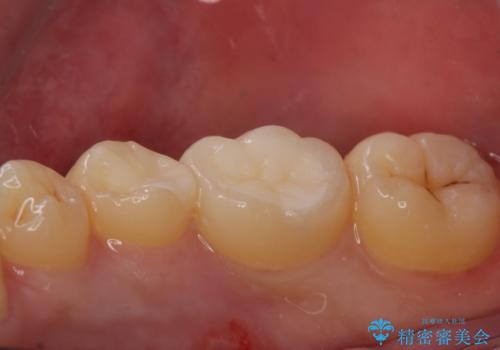

古い樹脂を除去してe-maxインレー

拡大鏡下で古い樹脂を除去し、虫歯がない事を確認してe-maxインレーで治療を行いました。

適合の良い詰め物が入りました。

セラミックは虫歯の再発のリスクが少ないです。